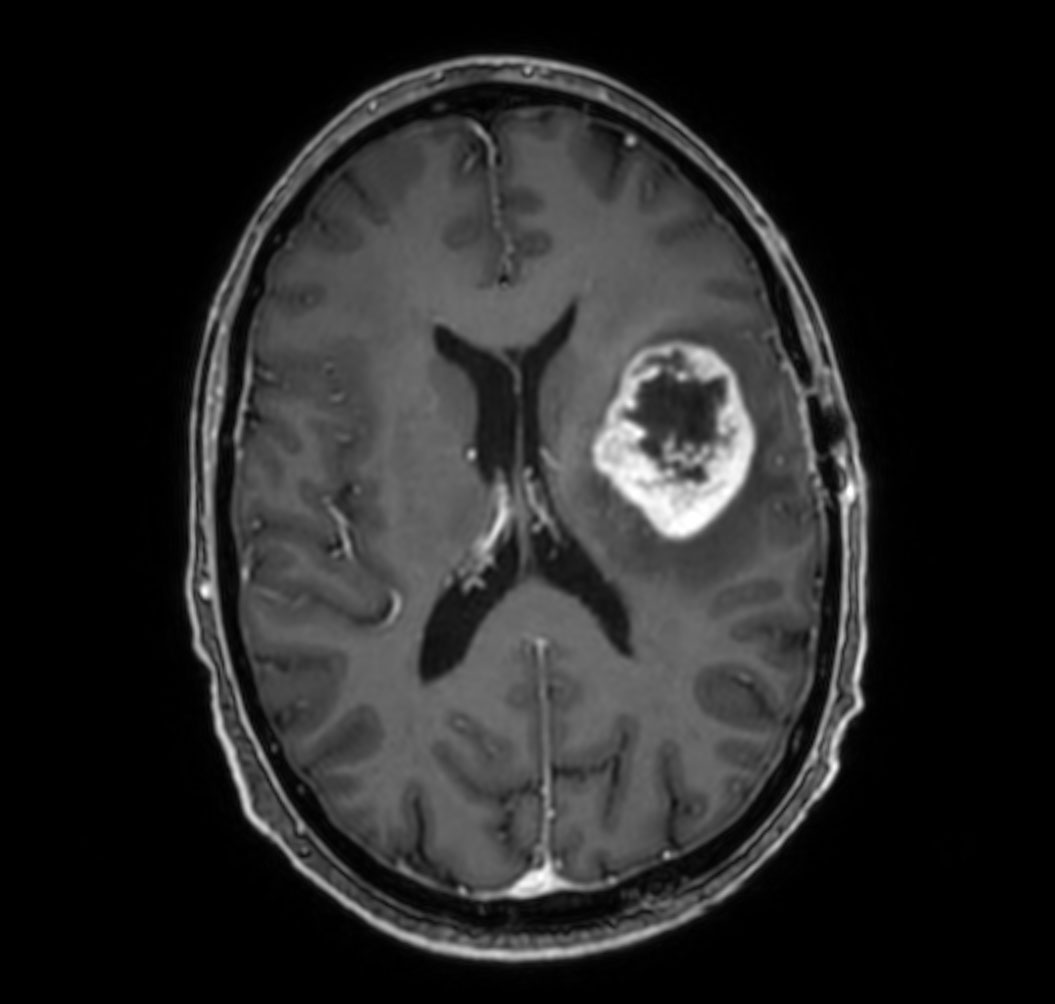

T1w 3D TFE